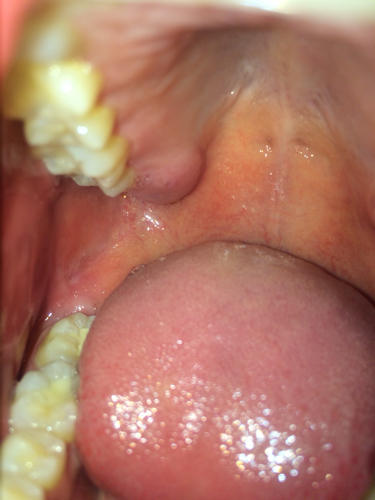

上颚长了一个疙瘩很硬,不疼

上颚长了个肉疙瘩可能是以下情况骨质畸形或黏膜增生这可能是天生的,如果不产生疼痛,可以不做特殊处理在需要制作假牙的情况下,可能需要切除上颚畸形组织病理性肿物囊肿上颚肿物可能是囊肿,需要进一步检查确认肿瘤包括良性肿瘤和恶...